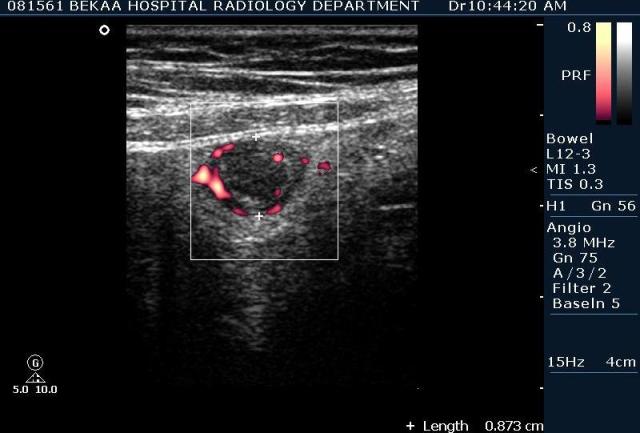

после начинаем производить хорошую компрессию датчиком попрося пациента сообщить в какой точке боль наиболее выражена; медленными движениями датчика сканируем область наибольших болевых ощущений и как правило находим утолщенный отросток. Лучше начинать с поперечной визуализации и идти к верхушке аппендикса что бы убедится что это аппендикс и он заканчивается, а не тонкая кишка (которая если и закончится то только переходя в слепую); потом надо аккуратно развернуть продольно датчик и посмотреть от верхушки аппендикса к слепой. Норма диаметра: 3-4 мм; 5-6 мм под вопросом (клиника решает; но я в катаральный аппендицит не верю); 7-8 мм и больше, не компремируемый (фиксированный отросток)-острый аппендицит! Помимо наличие утолщенного аппендикса; признака "бычьего глаза" (bull-eye sign) при поперечном сканировании; надо обращать внимание на присуствие аппендоколитов в просвете; деструкцию стенки и свободной жидкости в зоне интереса.